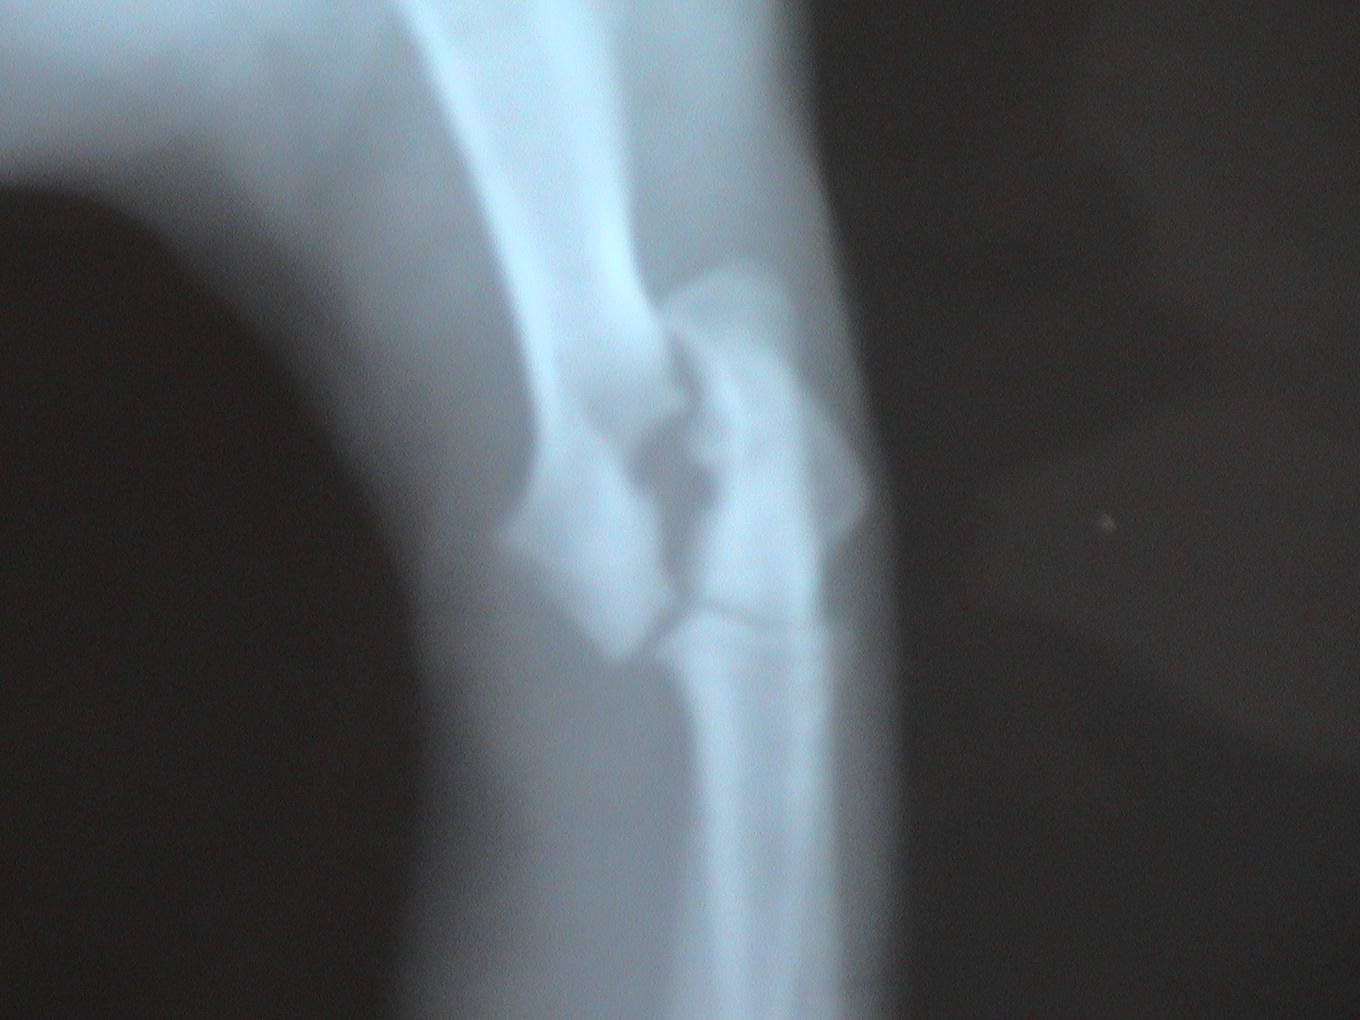

Dogs and cats commonly experience fractures secondary to trauma. The most common cause of the trauma is being hit by a car. Other trauma such as falls from furniture, jumping on unstable surfaces, leaping from a person's arms, etc. can also result in fractures. Below are some x-rays of some of the fractures we have seen at All Pets and their surgical correction using pins, plates, screws, and/or wires.